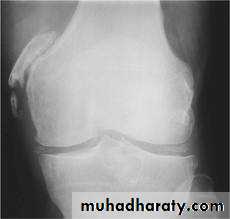

POST-TRA UMA TIC OSSIFICATION

Pellegrini-Stieda's disease of the medial femoral